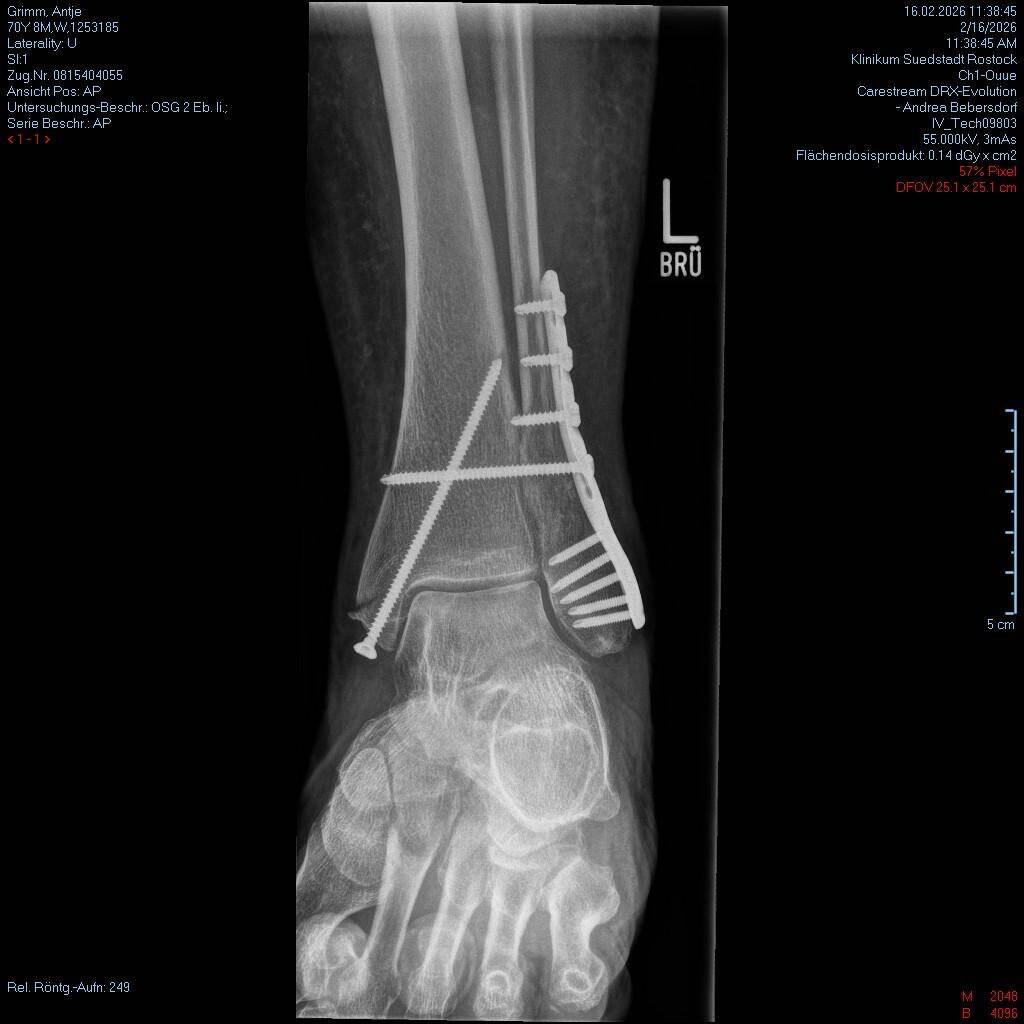

Vor zwei Jahren hatte ich mir bei einem Sturz in Folge einer Ohnmacht die linke Hand. Dieses Mal bin ich auf Glatteis ausgerutscht, gestürzt und habe mir eine Sprunggelenksluxations-

fraktur amRead more